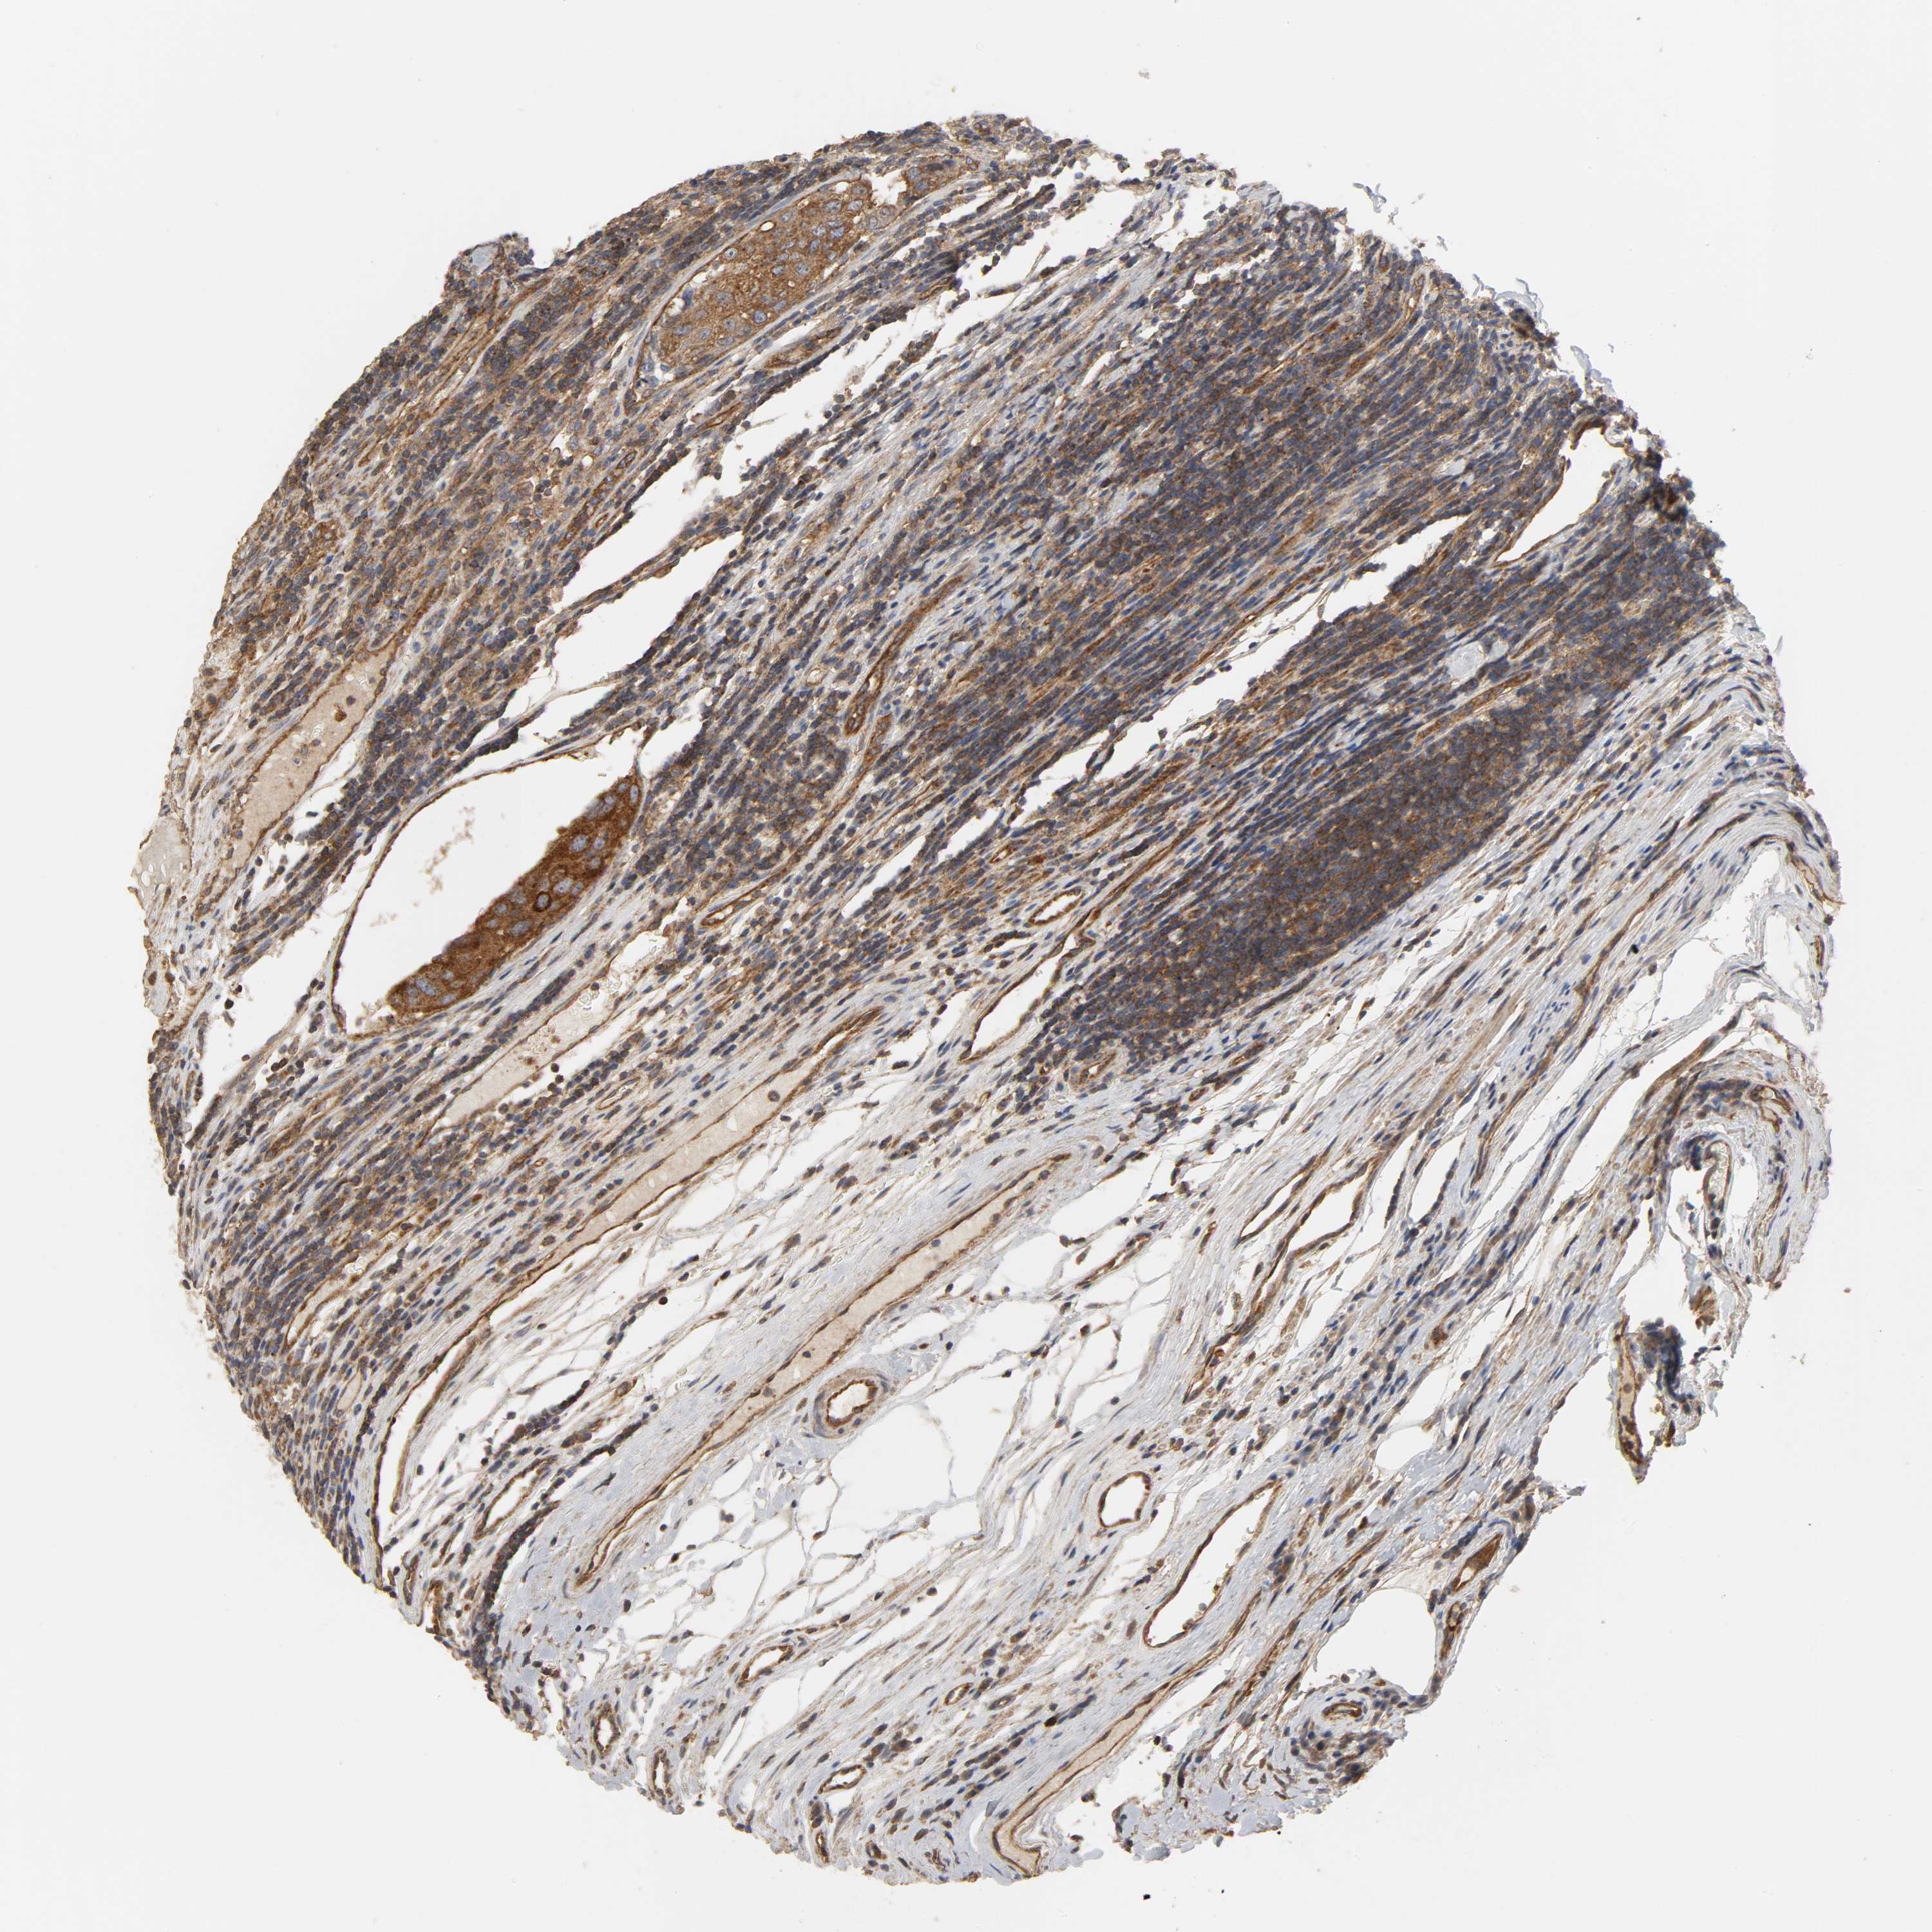

UROTHELIAL CANCER - Protein expressioni

A mouse-over function shows sample information and annotation data. Click on an image to view it in a full screen mode. Samples can be filtered based on level of antibody staining by selecting one or several of the following categories: high, medium, low and not detected. The assay and annotation is described here.

Note that samples used for immunohistochemistry by the Human Protein Atlas do not correspond to samples in the TCGA dataset.

Antibody stainingi

Antibody staining in the annotated cell types in the current human tissue is reported as not detected, low, medium, or high, based on conventional immunohistochemistry profiling in selected tissues. This score is based on the combination of the staining intensity and fraction of stained cells.

Each image is clickable and will lead to virtual microscopy that enables deeper exploration of all samples and also displays staining intensity scores, fraction scores and subcellular localization as well as patient and tissue information for each sample.

Antibody HPA015608

Antibody HPA019900

Antibody CAB004650

Staining

High

Medium

Low

Not detected

Intensity

Strong

Moderate

Weak

Negative

Quantity

>75%

75%-25%

<25%

None

Location

Nuclear

Cytoplasmic/membranous

Cytoplasmic/membranous,nuclear

Urothelial carcinoma, Low grade

Urothelial carcinoma, High grade